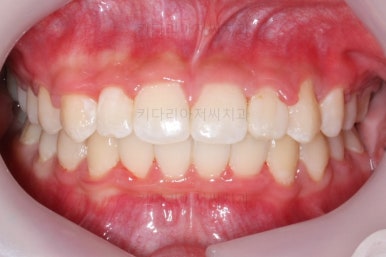

마찬가지로 부산교정치과 키다리아저씨치과에 처음 내원하셨을 당시의 입안 모습입니다.

화살표로 표시된 치아가 작은 앞니 부분인데 크기가 매우 작고 뾰족한 것을 볼 수 있어요. 유치가 아니고 평생 써야 하는 영구치입니다. 이러한 상태를 "왜소치"라고 표현하는데, 치아 크기의 문제로 여러 가지 문제점이 생길 수 있어요.

윗니 치아 사이에 틈이 생길 수 있습니다.(치아 크기가 모자란 만큼 틈이 있는 것이죠.)

아래 앞니가 삐뚤어질 수 있습니다.(비율상 아랫니가 상대적으로 커지기 때문에 삐뚤어지게 됩니다.)

미적으로 좋지 못합니다.